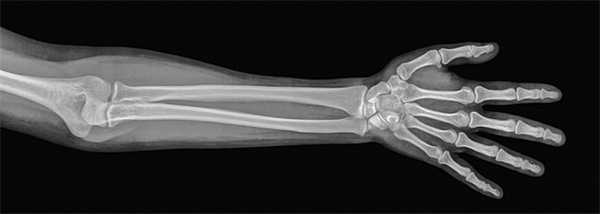

На рентгенограмме локтевого сустава в прямой проекции суставная поверхность плечевой кости имеет вид изогнутой линии соответственно очертаниям головки мыщелка и блока. Общая рентгеновская суставная щель плечелоктевого и плече-лучевого суставов зигзагообразная, толщина полосы «просветления» равна 2—3 мм. На нее накладывается тень локтевого отростка одноименной кости и видна суставная щель проксимального лучелоктевого сустава. В боковой проекции, когда предплечье с плечом составляет угол 90°, линия суставной щели локтевого сустава ограничена мыщелком плечевой кости, а с другой стороны — блоковидной вырезкой локтевой кости и головкой лучевой кости.

На рентгенограмме локтевого сустава в прямой проекции суставная поверхность плечевой кости имеет вид изогнутой линии соответственно очертаниям головки мыщелка и блока. Общая рентгеновская суставная щель плечелоктевого и плечелучевого суставов зигзагообразная, толщина полосы равна 2-3 мм. На нее накладывается тень локтевого отростка одноименной кости и видна суставная щель проксимального лучелоктевого сустава. В боковой проекции, когда предплечье с плечом составляет угол 90°, линия суставной щели локтевого сустава ограничена мыщелком плечевой кости, а с другой стороны - блоковидной вырезкой локтевой кости и головкой лучевой кости.

При рентгенографии локтевого сустава в боковой проекции (предплечье согнуто на 90°) линия рентгеновской суставной щели ограничена блоковидной вырезкой локтевой кости и головкой лучевой кости с одной стороны и мыщелком плечевой кости - с другой. При прямой проекции рентгеновская суставная щель зигзагообразная, имеет толщину 2-3 мм. Видна также суставная щель проксимального лучелоктевого сустава.